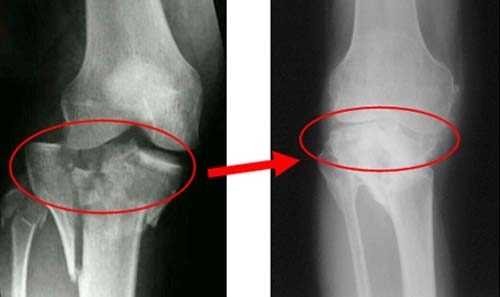

Обследование с помощью рентгена позволяет выявить отклонения от нормальных параметров сустава.

На снимке рентгена здорового колена костная структура однородна и целостна, суставная щель имеет равномерную достаточную толщину, нет смещений и деформаций, строение сустава симметрично, нет опухолей и прочих уплотнений тканей.

Рентгеновский снимок позволяет исследовать деформации, наличие остеофитов (отложение солей), трещины, инородные тела, состояние мягких тканей при первичной диагностике.

Если у пациента травмированы связки или сухожилия, межсуставная щель на изображении будет увеличена. При артрите ближайшие костные пластинки истончены, щель увеличена. Иногда на изображении толщина хрящевой прослойки сужена, кости увеличены и деформированы по краям, что показывает наличие артроза. Сужение межсуставной щели может указывать и на повреждение мениска.